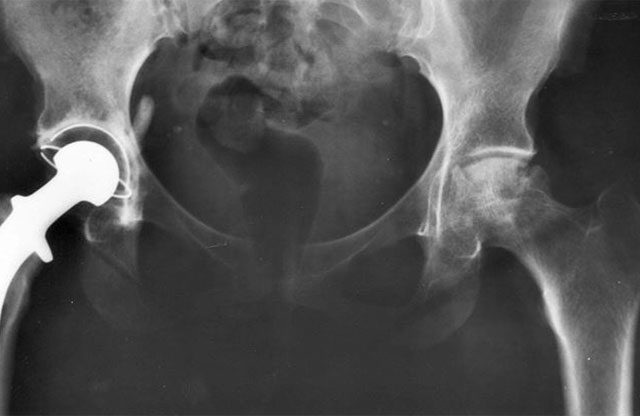

Nueva técnica mínimamente invasiva para colocar prótesis de cadera

La Unidad de Cadera de Icatme, del Hospital Universitario Dexeus, ha puesto en funcionamiento un nuevo abordaje quirúrgico para colocar prótesis de cadera de forma mínimamente invasiva. Se trata de una nueva técnica, que se conoce como Superpath, que lleva…